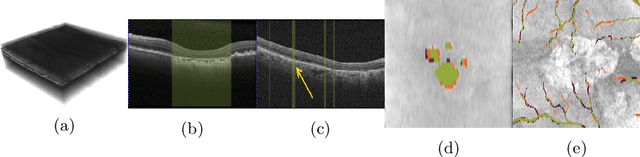

Abstract:In medical imaging, there are clinically relevant segmentation tasks where the output mask is a projection to a subset of input image dimensions. In this work, we propose a novel convolutional neural network architecture that can effectively learn to produce a lower-dimensional segmentation mask than the input image. The network restores encoded representation only in a subset of input spatial dimensions and keeps the representation unchanged in the others. The newly proposed projective skip-connections allow linking the encoder and decoder in a UNet-like structure. We evaluated the proposed method on two clinically relevant tasks in retinal Optical Coherence Tomography (OCT): geographic atrophy and retinal blood vessel segmentation. The proposed method outperformed the current state-of-the-art approaches on all the OCT datasets used, consisting of 3D volumes and corresponding 2D en-face masks. The proposed architecture fills the methodological gap between image classification and ND image segmentation.